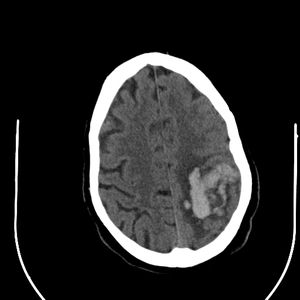

A 37-year-old female presented to the emergency room after awakening at 4 a.m. with right sided weakness. Neurological exam confirmed loss of strength on the right side, loss of sensation in the right upper extremity, and a positive right sided Babinski sign.